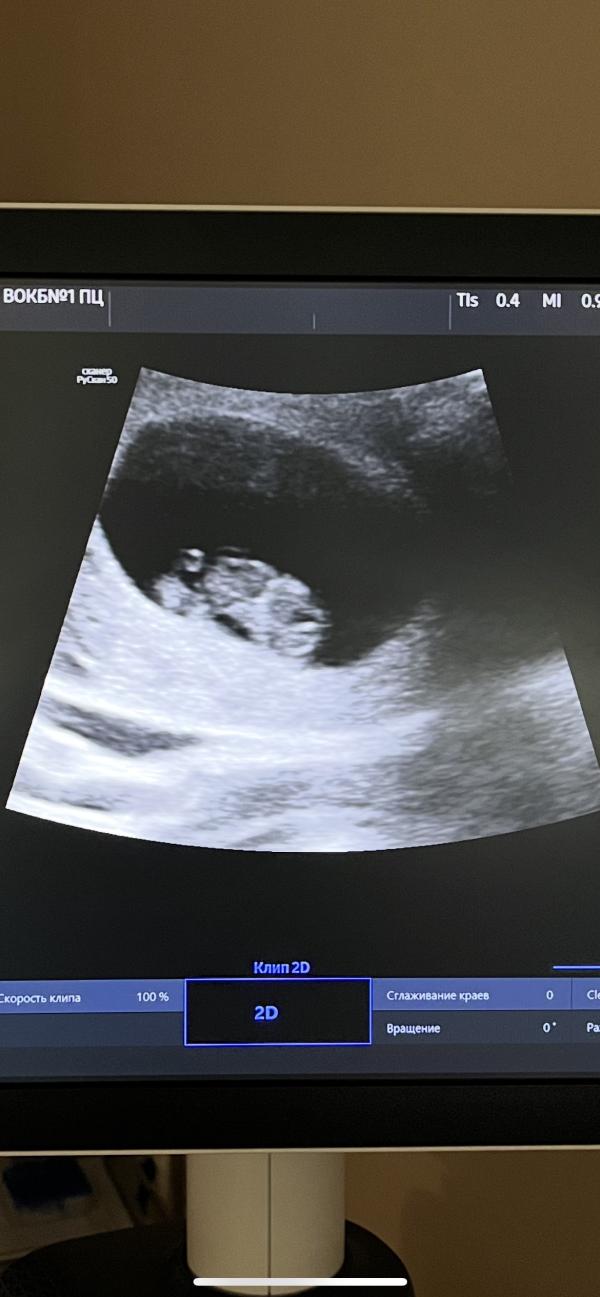

Маленький малышок 👶

КТР 22 ЧСС 165 - 9 неделек

Когда услышала сердцебиение на весь кабинет была безумно счастлива, непередаваемое ощущение 🥰